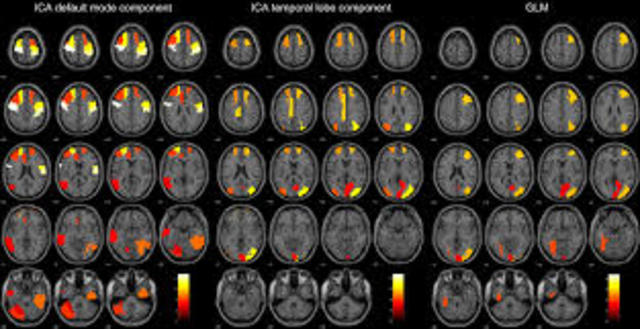

• Principio de resonancia magnética

Principio de resonancia magnética

• Sistema para uso en seres humanos de resonancia magnética

Sistema para uso en seres humanos de resonancia magnética